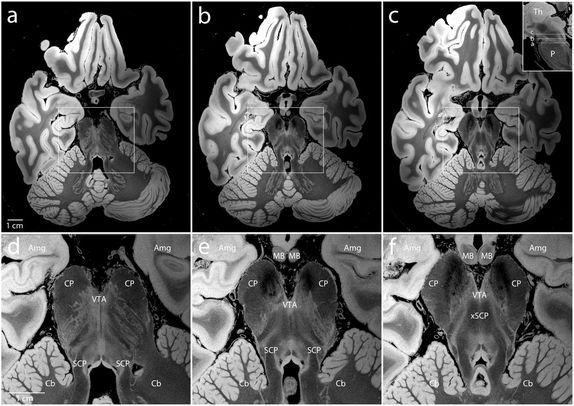

圖 | 皮質(zhì)下神經(jīng)解剖學(xué)描述,腦干、內(nèi)側(cè)顳葉和小腦前部的放大圖(來源:B.L. EDLOW ET AL/BIORXIV.ORG 2019)

研究人員使用不同的翻轉(zhuǎn)角(FA15°、FA20°、FA25°、FA30°)來生成多個(gè)合成體,每個(gè)合成體提供了不同的組織對比度。掃描的執(zhí)行時(shí)間超過 100 小時(shí)(每個(gè)翻轉(zhuǎn)角約 25 小時(shí)),生成一個(gè)超過 8TB 的數(shù)據(jù)集(每個(gè)翻轉(zhuǎn)角度約 2TB),然后通過專門的計(jì)算工具來進(jìn)行離線 MRI 重建和合成體創(chuàng)建。